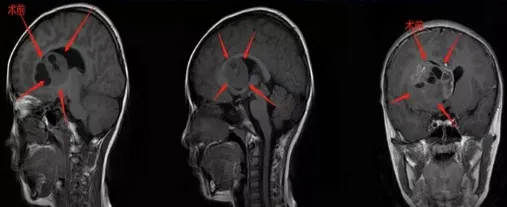

病情始于8岁女儿清晨的一句主诉:“妈妈,我头疼”。当时她正读幼儿园,平日喜爱与同伴上学,从未借故回避。但某天穿外套时,她首次提及头痛不适。了解孩子从不撒谎的习性,我立即请假带她就医,检查发现基底节区存在巨大占位性病变,肿瘤尺寸达50*41*37毫米,核磁共振影像表现令人忧心。确诊瞬间我情绪失控,难以接受现实,甚至不知该向医生询问哪些关键问题。首诊医生建议先行手术治疗。

手术成功:肿瘤全切与快速康复